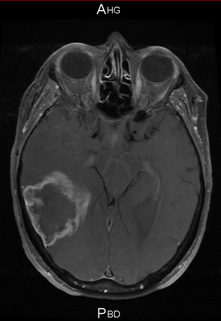

Mars 2011 Juin 2011

Mars 2011 : Patiente de 59 ans porteuse d’un glioblastome avec hémiplégie gauche ne permettant plus la marche.

D’avril 2011 à juin 2011 : bévacizumab 10 mg/kg en IV tous les 15 jours et témozolomide (150 puis 200 mg/m2/jour x 5 jours) à 4 semaines d’intervalle.

Récupération complète de l’hémiplégie.

Juillet/août 2011 : Radiochimiothérapie selon ‘’Stupp’’ en poursuivant le BVZ pendant la radiothérapie

Octobre 2011. Aucun déficit neurologique. OMS 0. Temozolomide adjuvant en cours et bévacizumab tous les 15 jours.